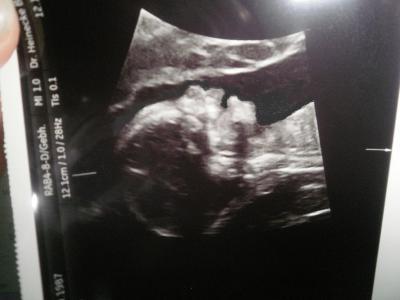

wollte euch mal meine maus zeigen

ich bin soooooooooooooooooooooo verliebt

Wow, das ist aber eine gute Bildqualität! Süß, wie deutlich man sie erkennt und schon schön am üben wie man schluckt würde ich jetzt vermuten...

ja sie hat mal ganz brav stillgehalten und mutti hat auch kurz das atmen sein lassen..wir haben aber 4 versuche gebraucht bis ich zufrieden war mit dem bild

Süß! Sehr schönes Seitenprofil.